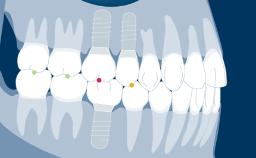

Moldagens de implantes são importantes para a confecção de próteses dentárias. O objetivo das moldagens de implantes é a transferência precisa da posição do implante intraoral para o laboratório dentário. É possível registrar a posição do implante com técnicas convencionais de moldagem analógica, ou com o uso de tecnologias digitais. Todas as técnicas de moldagem de implantes empregam uma variação da técnica de moldagem de arraste ou transferência, às vezes usada em prótese dentária convencional suportada por elementos dentários.

No caso de moldagens de implantes, um componente de alta precisão é usado para registrar a posição, o alinhamento e a orientação rotacional do implante. A moldagem, tanto se seguir um fluxo de trabalho convencional (ou seja, analógico) quanto digital, registra essa informação em relação aos tecidos duros e moles circundantes. Este módulo tratará das técnicas de moldagem convencionais e de todos os parâmetros envolvidos.

- definir os transferentes e técnicas de moldagem convencional de implantes